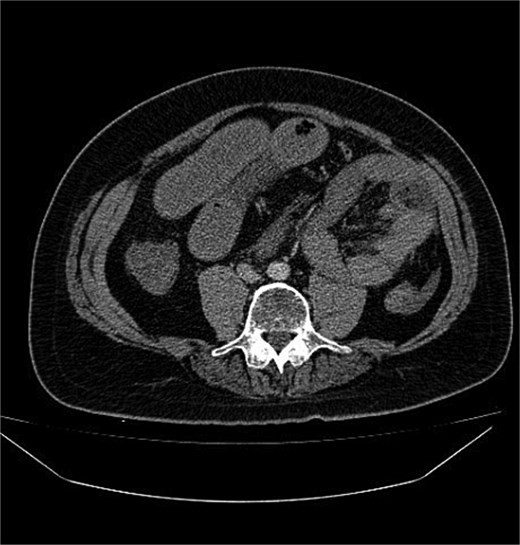

أظهرت الفحوصات والتصوير الطبي وجود فتق داخلي نادر أدى إلى احتباس جزء من الأمعاء الدقيقة داخل تجويف غير طبيعي في البطن، ما تسبب في انسدادها وانقطاع التروية الدموية عنها.

ويُعد هذا النوع من الحالات من الأسباب النادرة لانسداد الأمعاء، لكنه قد يتحول بسرعة إلى حالة مهددة للحياة إذا لم يتم التدخل الجراحي العاجل.

وخلال العملية اكتشف الأطباء أن جزءًا من الأمعاء الدقيقة تعرض للاختناق والتلف نتيجة الفتق الداخلي.

وقام الفريق الجراحي باستئصال نحو 60 سنتيمترًا من الجزء المتضرر من الأمعاء، ثم إعادة توصيل الأمعاء السليمة جراحيًا، مع معالجة سبب الفتق بشكل كامل.